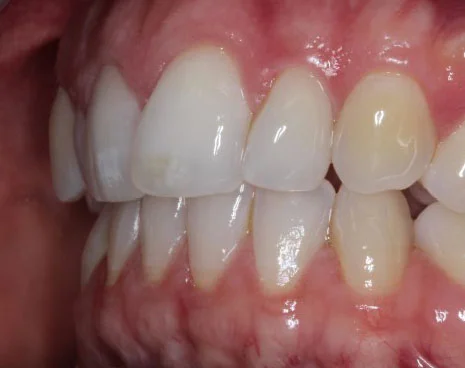

Our amazing Invisalign results

If you’re wondering whether Invisalign can really make a difference, simply take a look at these images below.

Case 5:

![]()